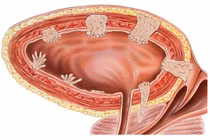

anh-2.jpg

Hình ảnh u bàng quang khổng lồ chèn ép thận gây thận ứ nước trên phim chụp - Ảnh BVCC

Kết quả khối u bàng quang của ông đã xâm lấn, chèn ép hai niệu quản gây thận ứ nước độ III, kèm suy thận. Ông N. được đặt ống sonde tiểu, hút ra một túi nước tiểu màu máu đỏ sậm.

Để cứu hai quả thận đang “chết đuối”, các bác sĩ đã thực hiện dẫn lưu thận qua da. Khi chức năng thận ổn định, ông được cắt bàng quang tận gốc và tái tạo bàng quang bằng ruột non để loại bỏ khối u ác tính.